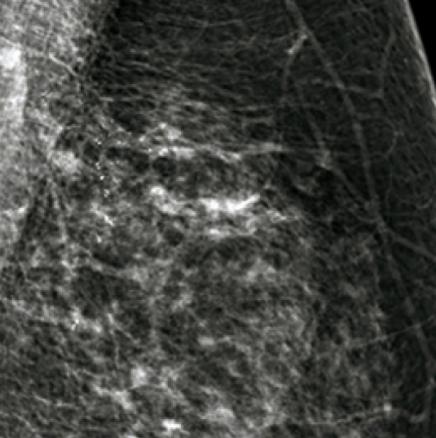

© Sylvie Lemery - La Revue du Praticien Microcalcifications irrégulières, distribution triangulaire. BIRADS 5. Histo CCI + CCIS haut grade.